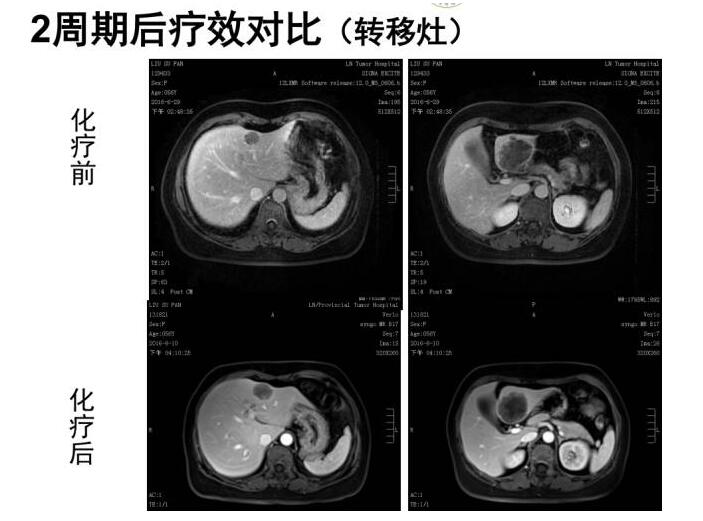

FOLFOX方案术前新辅助化疗(奥沙利铂150mg,5Fu4.5g/48小时泵入),双周方案,2个周期后评估疗效;

2周期后,与2016.6.29前片对比:肝左叶一肿块(较小者)较前增大,另外一病灶大小变化不明显,评效增大SD。肿瘤标记物水平持续升高。

患者新辅助治疗无效